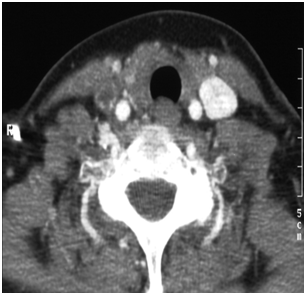

She was discharged home with a course of oral antibiotic and warfarin until her outpatient review. A follow-up CT scan performed 1month later failed to show resolution of the thrombosis with complete occlusion of the right IJV (Figure 2).

Figure 2 CT scan confirmation of right IJV thrombosis (arrow).

The patient remained on warfarin for a further 6 months after the event, and was then discontinued. She remained under regular review by the gastroenterologist to monitor her liver function.  The conclusion of all teams involved in this patient’s care was that this was an idiopathic IJV thrombosis. Underlying soft tissue infection was thought to be a possibility, given the clinical findings, but a definite diagnosis was never made.